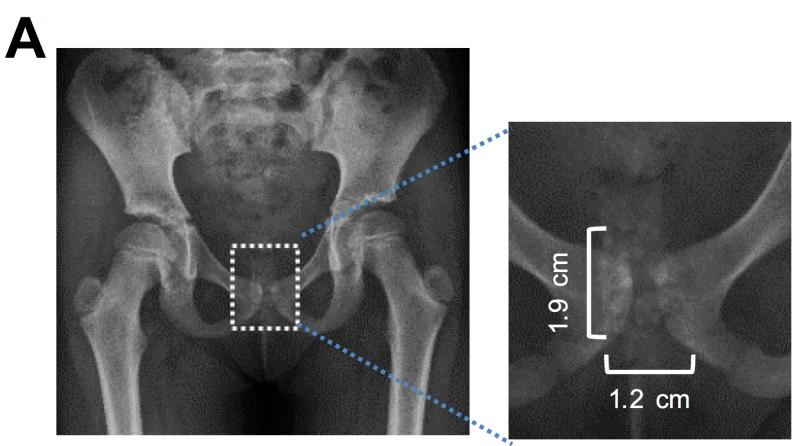

Vaginal discharge in prepubescent girls is not an uncommon problem in pediatric outpatient practice. Among its various etiologies, foreign body lodgement is quite frequent in this age group. Diagnosis is sometimes forthcoming after history and physical exam, and the removal of the foreign object is followed by a prompt resolution of symptoms. However, in rare circumstances, an intravaginal foreign body may mimic other pathologies, including infections and neoplasms, as well as raising suspicion for child abuse. In such cases, diagnosis may remain unclear even after laboratory tests and imaging studies. We describe a seven-year-old girl with vaginal discharge, who needed inpatient admission, multiple imaging studies and, finally, exploration under anesthesia to confirm the diagnosis of foreign body (fecal mass) lodgement and its removal. This is a very rare case where the lodgement of an intravaginal fecal mass in a child led to such protracted symptoms requiring extensive diagnostic and therapeutic maneuvers, in the absence of any structural abnormality of the urogenital tract.

青春期前女童的阴道分泌物在儿科门诊实践中并非罕见问题。在其各种病因中,异物存留在这个年龄组相当常见。有时通过病史和体格检查即可做出诊断,取出异物后症状会迅速缓解。然而,在罕见情况下,阴道内异物可能会模仿其他病理情况,包括感染和肿瘤,同时也会引发对虐待儿童的怀疑。在这种情况下,即使经过实验室检查和影像学研究,诊断仍可能不明确。我们描述了一名七岁有阴道分泌物的女童,她需要住院,进行多项影像学检查,最后在麻醉下探查以确诊异物(粪块)存留并将其取出。这是一个非常罕见的病例,儿童阴道内粪块存留导致了如此迁延的症状,需要进行广泛的诊断和治疗操作,而泌尿生殖道并无任何结构异常。